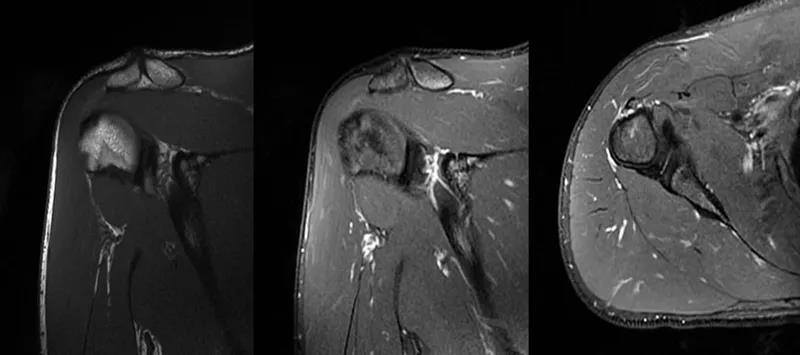

2、MRI检查MRI目前是诊断肩袖疾病中最常用的检查,可以直观的观察肩袖肌腱。

图21 斜冠状位(临床常用)a.T2,b.T1

图22 斜矢状位 a.冈上肌出口,肩袖诊断不如斜冠状位;b.冈上肌及肌腹脂肪浸润成度,评估手术与否

图23 横断位a.正常肩胛下肌;b.肩胛下肌损伤